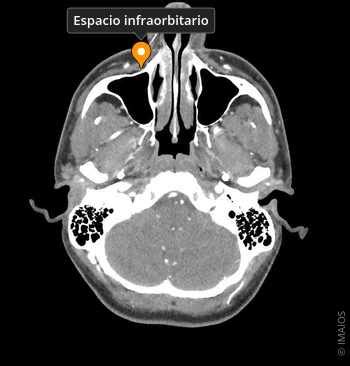

Canal Infraorbitario visible en Tomografía Computarizada (TC)

El canal infraorbitario está localizado en la porción anterior del hueso maxilar, en su cara orbitaria. Su trayecto comienza en el surco infraorbitario, que se convierte progresivamente en canal cerrado y termina en el foramen infraorbitario, visible en la cara anterior del maxilar.

El canal infraorbitario es visible mediante técnicas de imagen como la tomografía computarizada (TC) de alta resolución y la resonancia magnética (RM). Se han descrito variantes en el trayecto, la longitud, la orientación y el número de ramificaciones del canal infraorbitario.